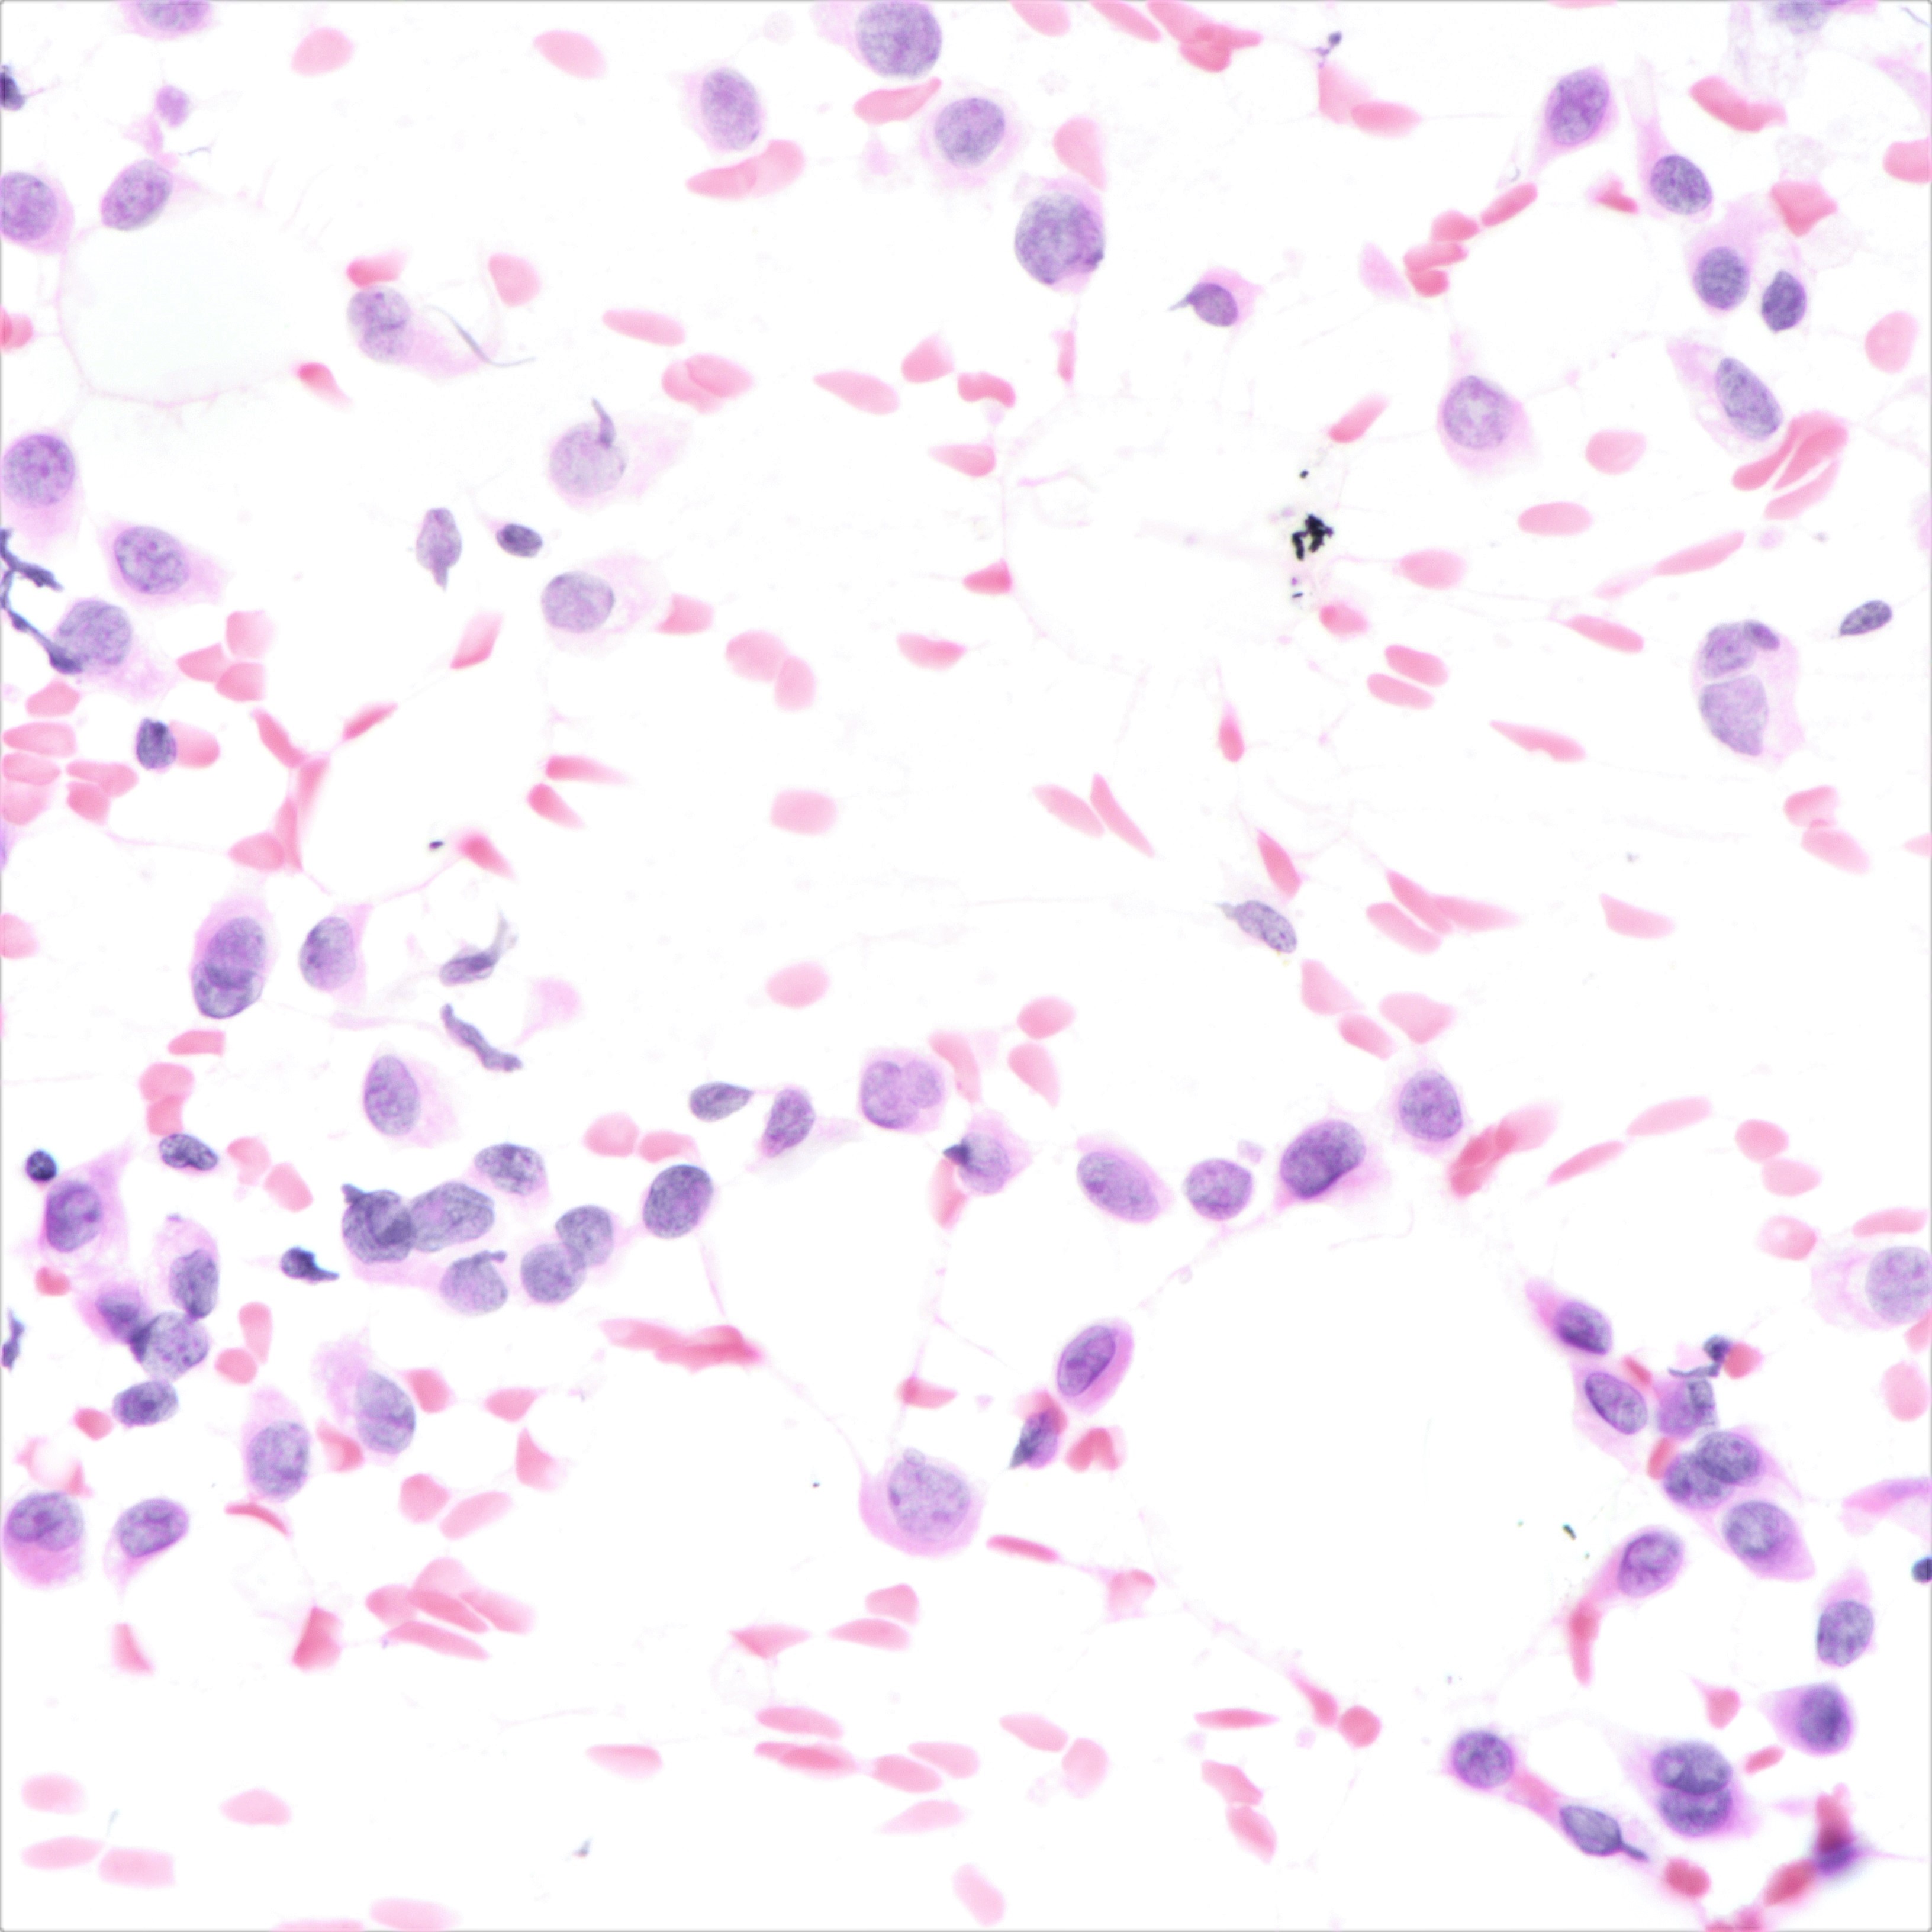

Cytology description

- Cellularity can be low

- Tumor cells arranged in chains, single files or as single cells

- Tumor cells arranged in small chains are helpful clues

- Nuclear atypia mostly mild

- Nuclei round to oval and eccentric

- Cytoplasm scanty with a high nuclear / cytoplasmic ratio

- Occasional intracytoplasmic vacuolations may be seen

- Cytologic features can resemble mesothelial cells in effusion fluid (Diagn Cytopathol 2012;40:311)

Cytology images